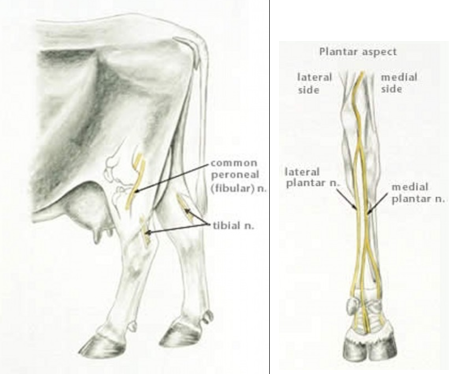

What are the nerve blocks for the hind feet in cattle

Superficial peroneal nerve

Deep peroneal nerve

Medial and lateral plantar nerve